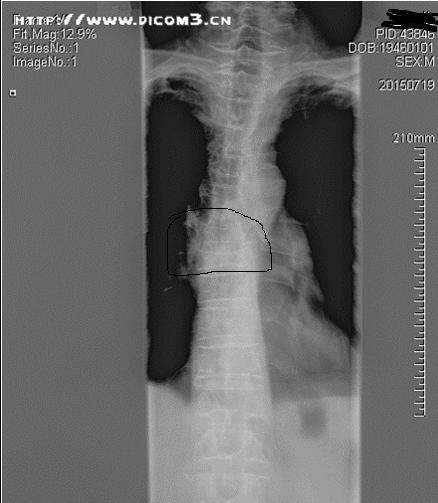

胸椎正位片(标识处为骨折部位)

来诊时,患者已经12天未排大便,查体:腹部膨隆,脐上压痛,肠鸣音稍亢进,舌红苔黄厚腻,脉弦滑,见患者进诊室时就一直含胸驼背,追问患者病情,自述其后背部隐痛不适,不敢直腰,进一步扩大查体范围,查脊柱发现,胸8、9棘突尖、椎体两侧旁压痛叩击痛明显,建议患者行胸椎正侧位X片检查,患者满脸狐疑,“明明是肚子不好,拍什么胸椎片啊”,还好,之前攒了点人品,这时起了作用,患者虽然疑心重重,但最终还是听从了我的建议,拍片检查示:胸8.9压缩性骨折,再追问既往病史,患者无明显外伤史,但此前曾长期口服激素类药物,病情叙述到此打住,问题来了,患者好好的怎么就骨折了呢?即便有骨折,又与大便不通又有什么关系呢?

胸椎侧位片(标识处为压缩性骨折部位)